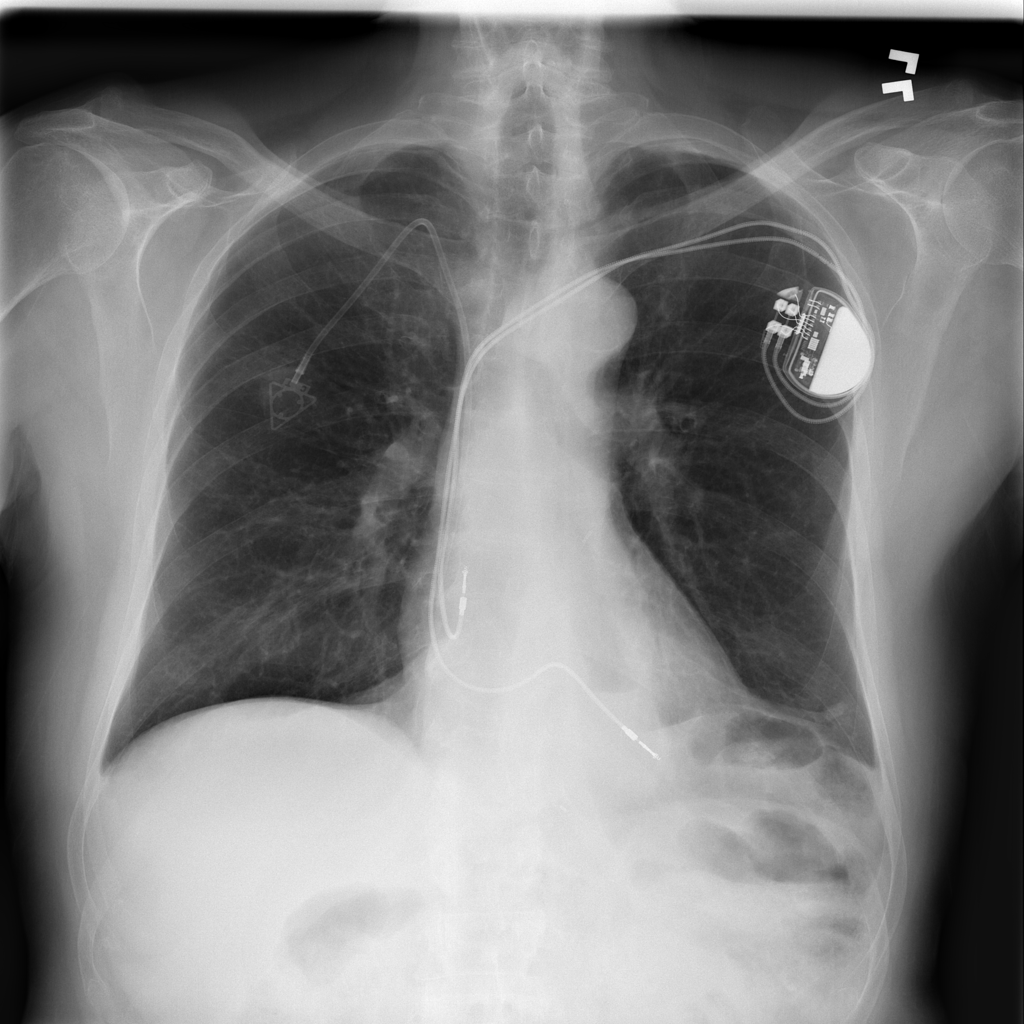

Support Devices

Support devices on chest X-ray include lines, tubes, and implanted hardware whose position may affect safety and management.